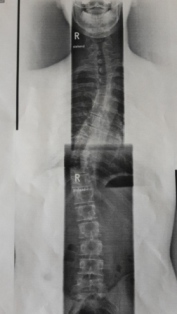

- Rechtskonvexe Thorakolumbale Skoliose von 28 Grad (Bild im Anhang)

Ansicht von vorne

20151219_150853.jpg (26.85 KiB) 10877 mal betrachtet

20151219_150925-1.jpg (28 KiB) 10877 mal betrachtet

Wie Lady S sagte: Kann sein oder auch nicht sein. Der Verlauf ist bei jedem unterschiedlich und schwer vorherzusagen. Eine extreme Verschlechterung in kurzer Zeit, wie dies in der Jugend bei Wachstumsschüben passieren kann, ist unwahrscheinlich. Bei einer Verkrümmung ab 30° im Erwachsenenalter tritt nach Erfahrungswerten durchschnittlich eine Verschlechterung von 1° pro Jahr auf. Es gibt aber Erwachsene, bei denen das nicht passiert und welche, bei denen schlimmere Verschlechterungen auftreten. Verschlechterungen bei einer Skoliose unter 30° sind nicht so häufig, aber auch nicht auszuschließen. Du kratzt so gerade an dieser 30°-Grenze - vor allem sind die Messwerte immer etwas ungenau, sodass man von einer Messtoleranz von 5° ausgeht; hinzu kommt, dass bei dir offenbar Teilaufnahmen gemacht und übereinander gelegt wurden (oder seh ich das falsch?), was noch mehr zu Ungenauigkeiten führen kann.

Er hat auch nochmal meine Krümmung nachgemessen und auch meine Gegenkrümmungen.

Hauptkrümmung: Thorakolumbal rechtskonvex 28 Grad Rotation: II

Gegenkrümmung: Thorakal links 28 Grad Rotation: I

Gegenkrümmung: Lumbal links 13 Grad Rotation: I